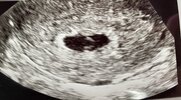

Dziewczyny ja po wizycie.

kamień z serca… chociaż trochę

przestałam się tak strasznie denerwować i dobrze ze poszłam dziś czyli tydzień wcześniej bo okazało się ze moja gin za tydzień ma urlop.

Pęcherzyk jest większy, ciałko żółte jest, serduszka jeszcze nie ma ale co najważniejsze nie widać zaśniadu na obrazie i mam nadzieje ze tak już zostanie

kolejna wizytę mam dopiero w sierpniu. Nie wiem jak ja tyle wytrzymam

Załączniki